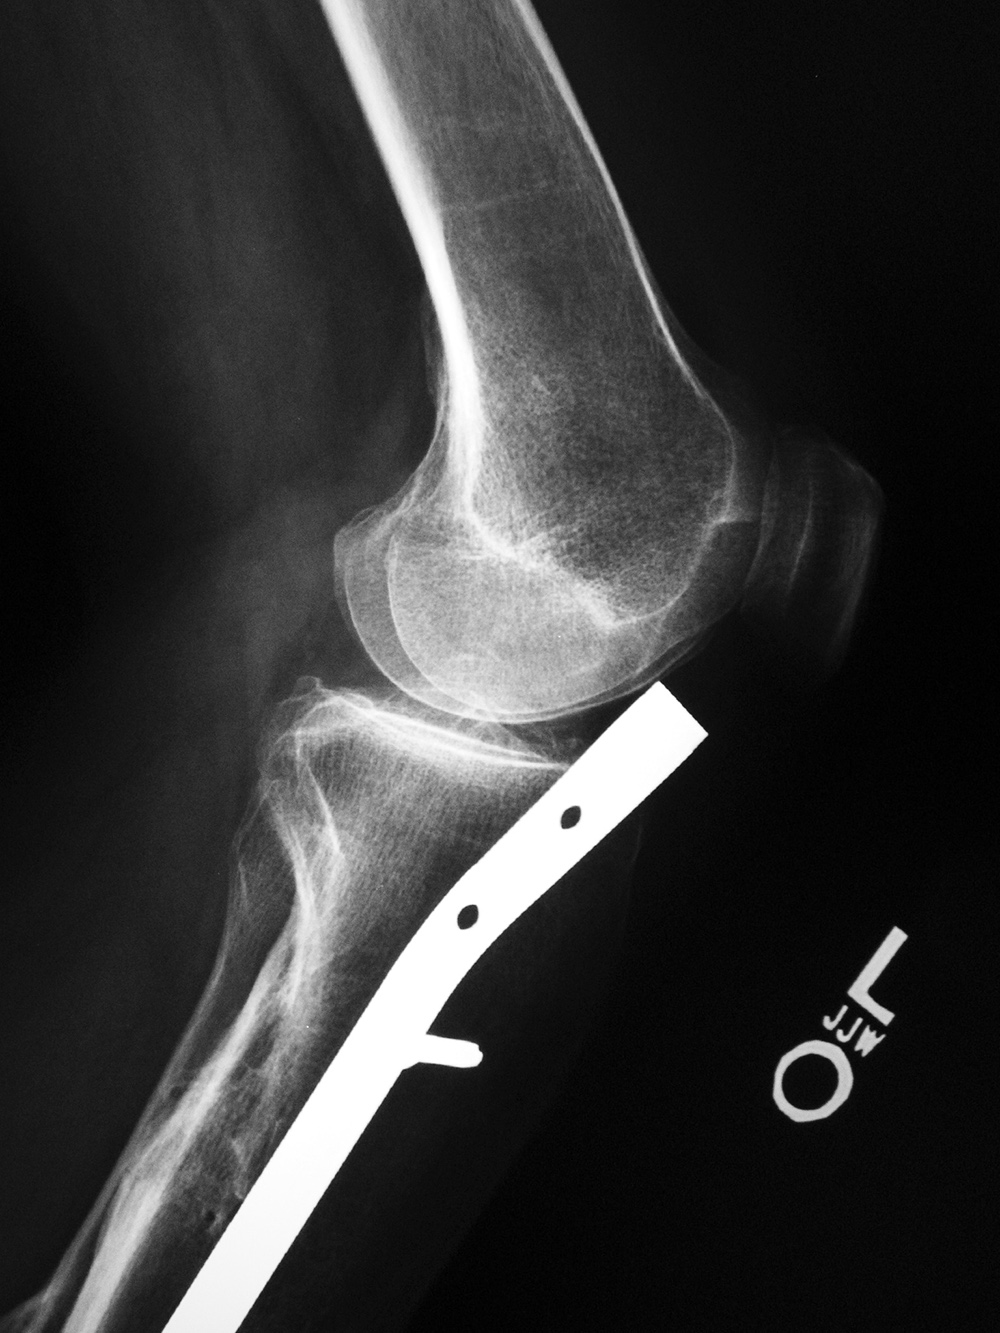

Left knee antegrade intramedullary rod displacement into knee joint |